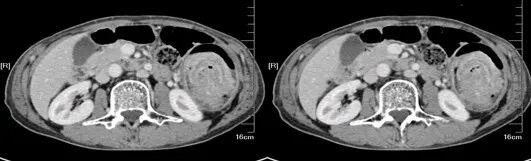

大肠癌

大肠癌是常见的恶性肿瘤,包括结肠癌和直肠癌。大肠癌的发病率从高到低依次为直肠、乙状结肠、盲肠、升结肠、降结肠及横结肠,近年有向近端(右半结肠)发展的趋势。其发病与生活方式、遗传、大肠腺瘤等关系密切。发病年龄趋老年化,男女之比为1.65:1。

升结肠癌并广泛转移